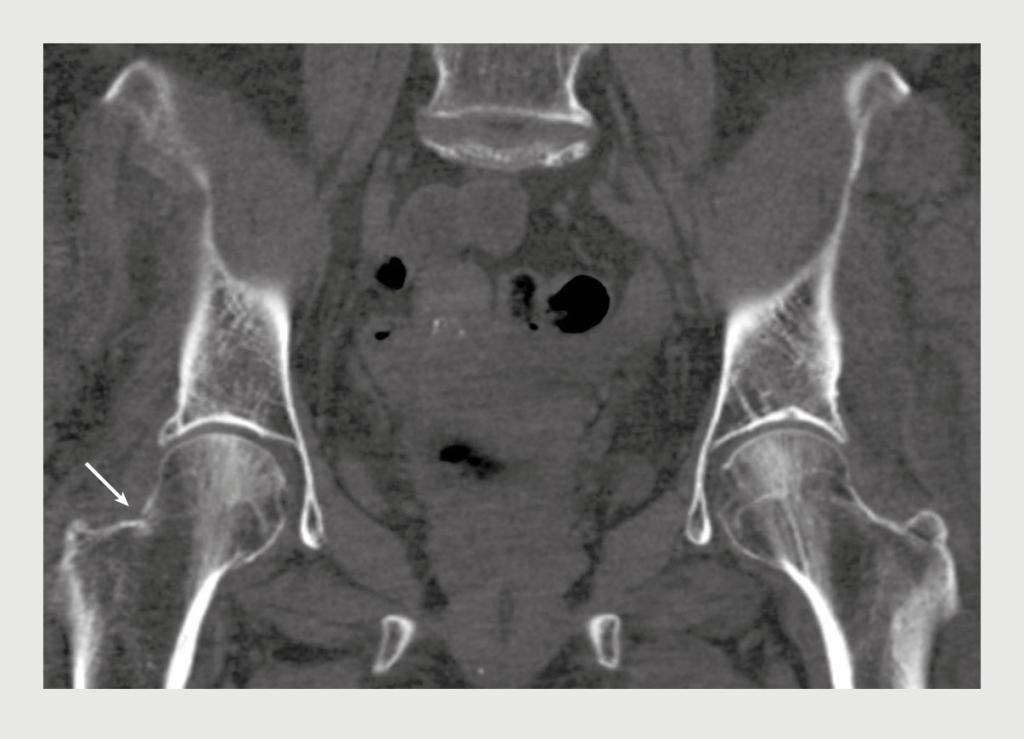

Figuur 2

CT-scan van het bekken van patiënt A

Figuur 2 | CT-scan van het bekken van patiënt A

Coronale opname van een CT-scan van het bekken van patiënt A. Er is een partiële fractuurlijn zichtbaar die haaks staat op de laterale cortex van de rechter femurhals, passend bij een stressfractuur van het spanningstype. Rond de fractuur is enige sclerose zichtbaar.